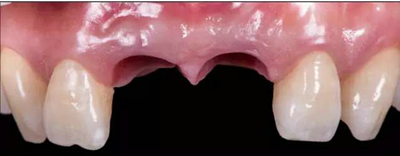

根據(jù)過渡義齒的螺絲孔及開口位置,最終修復(fù)方式為個(gè)性化全瓷基臺(tái)+全瓷冠。由于粘接界面位于齦下,粘接劑殘留可能會(huì)誘發(fā)種植體周圍發(fā)炎發(fā)生,因此本病例首選螺絲固位的方式。

角度螺絲通道全瓷基臺(tái)一體冠制作(機(jī)械連接,無粘接劑;原廠配件;更好的穿齦形態(tài);方便取下維護(hù))。

種植過渡義齒是醫(yī)技患三者共同合作的結(jié)果,通過觀察過渡義齒的形態(tài)、牙齦袖口、咬合等,為最終義齒修復(fù)奠定了基礎(chǔ)。本案例經(jīng)醫(yī)技患三方溝通討論,最終確定治療方案:Asc角度螺絲通道全瓷基臺(tái)一體冠進(jìn)行種植固定修復(fù)。